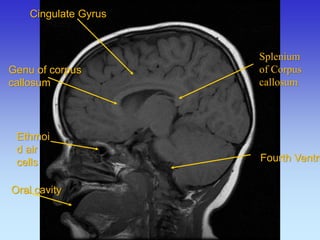

Cingulate Gyrus

Genu of corpus callosum

Ethmoid air cells

Oral cavity

Splenium of Corpus callosum

Fourth Ventricle